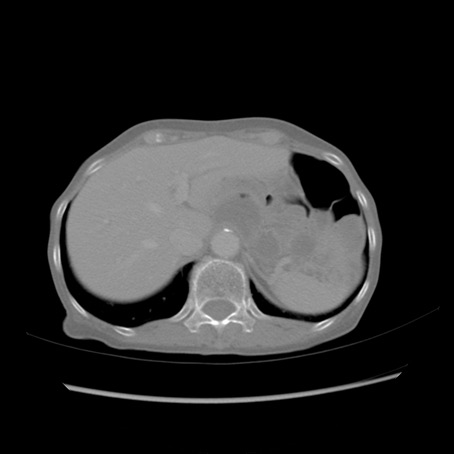

症例25(横断像)

【症例】80歳代女性

【主訴】胸のつかえ感

【現病歴】約9時間前に食後から胸のつかえた感じあり、嘔吐あり、来院。

【既往歴】胃癌(全摘)、胆摘、虫垂炎

【身体所見】心窩部に圧痛あり、反跳痛なし。

【データ】WBC 5700、CRP 0.05